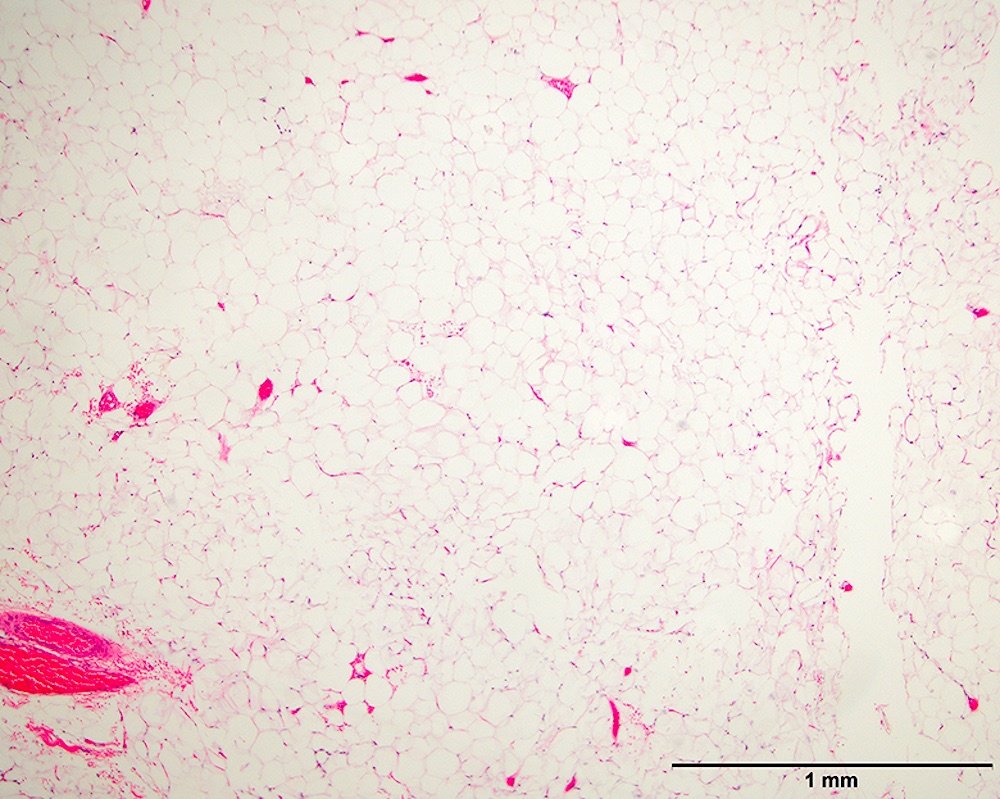

Microscopic (histologic) images

Contributed by Michael Clay, M.D., Melanie Bourgeau, M.D. and AFIP

Morphologic variability:

Metaplastic change:

- Lipoma-like subtype

- Most common subtype

- Scattered atypical cells may be diffuse or exceedingly rare

- Frequently contains lipoblasts

- Grossly, can be indistinguishable from lipoma

- Typically multilobulated and well circumscribed

- Rarely are grossly infiltrative

- Marbled yellow cut surface in lipoma-like lesions, with more firm / fibrotic white areas grossly in lesions with less adipocytic differentiation (Semin Diagn Pathol 2019;36:112)